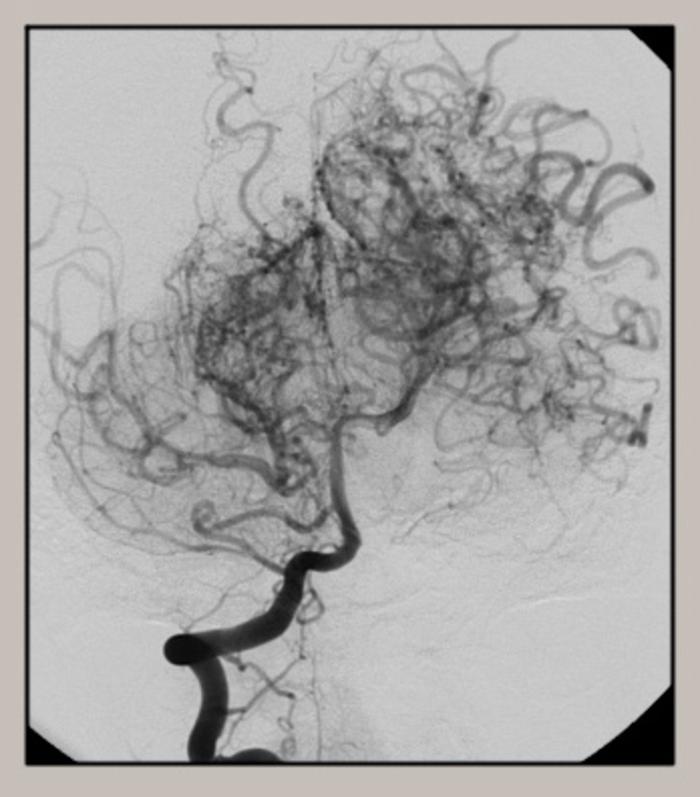

47岁,男性,右侧类烟雾病.行颞浅大脑中搭桥 颞肌贴覆 硬膜翻转术.